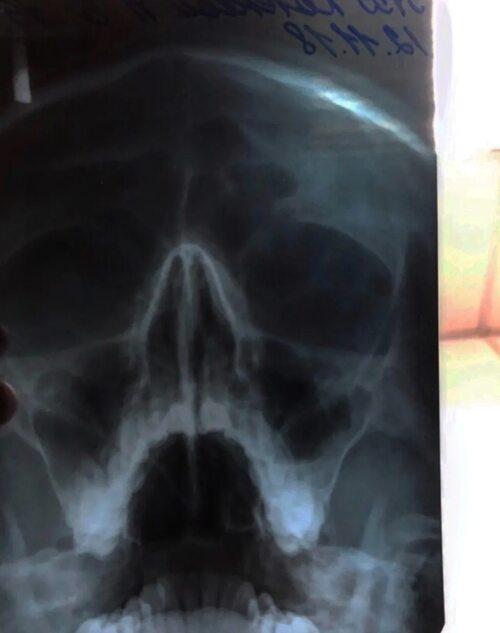

Фото кривой перегородки носа

Ниже представлены фотографии различных случаев кривой перегородки носа. Ознакомьтесь с этими изображениями, чтобы получить представление о том, как выглядит эта проблема: